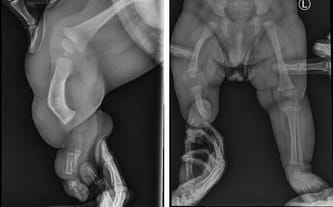

23 marca odbyliśmy konsultację z doktorem Paleyem w Paley European Institute w Warszawie. Podczas wizyty potwierdził, że wada Leosia jest bardzo trudnym i rzadkim przypadkiem, co wynika z połączenia dwóch poważnych schorzeń: hemimelii strzałkowej (czyli braku kości strzałkowej, skrócenie kończyny, deformacja stopy) oraz wrodzonego niedorozwoju kości udowej.

Zazwyczaj dzieci zmagają się tylko z jednym z nich, natomiast u Leona występują oba jednocześnie, co sprawia, że leczenie będzie długie i wieloetapowe. Bez operacji różnica w długości nóżek będzie się z czasem pogłębiać i w dorosłym życiu może sięgnąć nawet około 30 cm (!), co znacząco wpłynęłoby na jego sprawność i codzienne funkcjonowanie.

Podczas wizyty wykonano nowe zdjęcia RTG. Na ten moment różnica długości nóżek wynosi już 9,5 cm… To pokazuje, jak dynamicznie postępuje wada i jak pilnie Leon potrzebuje specjalistycznego leczenia.

Leoś urodził się ze znacznie krótszą prawą nóżką. Lekarze przewidują, że różnica długości może osiągnąć nawet 30 centymetrów. Skrócona kość udowa, skrócona kość piszczelowa, brak kości strzałkowej, zdeformowana stopa z trzema złączonymi paluszkami… Diagnoza: hemimelia strzałkowa – wada, która zabiera beztroskie dzieciństwo i odbiera szansę na normalny krok.